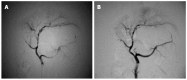

Methods: Twenty-one healthy Guizhou miniature pigs were randomly divided into three experimental groups and three control groups. The pigs in the three experimental groups were subjected to hepatic arterial perfusion with 7, 12 and 17 mL of 80% alcohol, respectively, while those in the three control groups underwent hepatic arterial perfusion with 7, 12 and 17 mL of saline, respectively. Hepatic arteriography and direct portal phlebography were performed on all animals before and after perfusion, and the portal venous pressure and diameter were measured before perfusion, immediately after perfusion, and at 2, 4 and 6 wk after perfusion. The following procedures were performed at different time points: routine blood sampling, blood biochemistry, blood coagulation and blood ammonia tests before surgery, and at 2, 4 and 6 wk after surgery; hepatic biopsy before surgery, within 6 h after surgery, and at 1, 2, 3, 4 and 5 wk after surgery; abdominal enhanced computed tomography examination before surgery and at 6 wk after surgery; autopsy and multi-point sampling of various liver lobes for histological examination at 6 wk after surgery.

Results: In experimental group 1, different degrees of hepatic fibrosis were observed, and one pig developed hepatic cirrhosis. In experimental group 2, there were cases of hepatic cirrhosis, different degrees of increased portal venous pressure, and intrahepatic portal venous bypass, but neither extrahepatic portal-systemic bypass circulation nor death occurred. In experimental group 3, two animals died and three animals developed hepatic cirrhosis, and different degrees of increased portal venous pressure and intrahepatic portal venous bypass were also observed, but there was no extrahepatic portal-systemic bypass circulation.